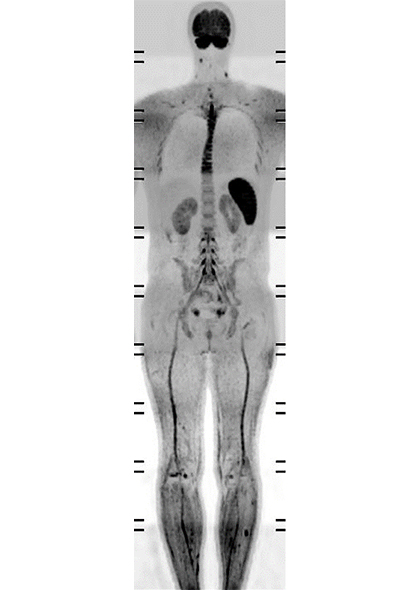

Классическим методом визуализации злокачественных новообразований является Позитронно-Эмиссионная Томография (ПЭТ). Несмотря на то, что ПЭТ позволяет с высокой точностью и разрешением обнаружить метастазы, этот метод сопряжен с лучевой нагрузкой и другими рисками, связанными с введением радиофармпрепарата (РФП). Поэтому в настоящее время активно ведется разработка новых МРТ методик, позволяющих получать ПЭТ-подобные изображения для своевременной и безопасной диагностики онкологических заболеваний. Одной из таких методик является МРТ последовательность DWIBS (Diffusion weighted imaging with background suppression). Эта методика основана на совмещение обычной диффузионно взвешенной МРТ с дополнительным коротким временем инверсии (аналогично STIR изображениям), что позволяет эффективно избавляться от фоновых сигналов от структур, не ограничивающих диффузию воды. Таким образом, изображения DWIBS похожи функционально и визуально на ПЭТ, что в совокупности с быстрым временем сканирования без задержки дыхания дает возможность использовать DWIBS для эффективного и безопасного онкоскрининга всего тела.

Специалисты медицинского радиологического научного центра им. А.Ф. Цыба считают данную методику особенно перспективной в оценке метастазов в кости [1].

Метастатическое поражение скелета встречается на фоне рака молочной железы и предстательной железы в 70–80% случаев аутопсий Более чем у половины онкопациентов отдалённое метастазирование начинается с поражения костей [2]. МРТ зарекомендовала себя эффективным методом В выявлении метастатического поражения скелета МРТ демонстрирует более высокие показатели чувствительности и специфичности (90,5 и 95% соответственно), чем сцинтиграфия (72,9 и 93,9%), и, по крайней мере, сопоставимыми ― с совмещённой ПЭТ-КТ с холином (89,7 и 96%) [3]. При этом, несомненно, помимо постановки первичного диагноза, интерес врачей рентгенологов заключается и в оценке ответа тех или иных злокачественных очагов на проводимое лечение, а также наблюдение их в динамике. Для этого одним из наилучших вариантов является количественная оценка ограничения диффузии (параметр ИКД, ADC). До этого времени достоверных данных о том, как соотносятся значения ADC, измеренные при помощи обычной DWI и DWIBS не было, что не давало уверенности в использовании DWIBS для их расчета. Поэтому, совместно с Philips Clinical Science врачи центра им. А.Ф. Цыба провели исследование [4] и доказали, что значения ADC, измеряемые с помощью DWI и DWIBS не отличаются (исследования проводилось как на пациентах, так и на МР совместимых фантомах). Таким образом, обновленный протокол DWIBS c возможностью расчета значений ADC может успешно использоваться в клинической практике.

Изображение предоставлено сотрудниками медицинского радиологического научного центра им. А.Ф. Цыба